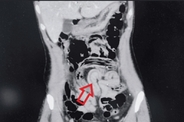

더지엠뉴스 이남희 기자 | 극심한 복통으로 병원을 찾은 20대 여성이 맹장 수술을 받은 직후 구토 과정에서 살아 있는 회충을 입으로 토해낸 사례가 국제 학술지에 보고됐다. 장 속에 숨어 있던 기생충이 충수 안쪽까지 파고들어 염증을 일으킨 뒤 위 방향으로 역행한 것으로 추정되면서, 위생 관리와 정기적인 구충의 필요성이 다시 떠오르고 있다. 24일 국제 의학 저널 큐레우스에 따르면, 필리핀 국적의 29세 여성 A씨는 심한 배 통증을 호소하며 사우디아라비아 킹 살만 병원 응급실을 찾았다. A씨가 처음 느낀 통증은 배꼽 주변에서 시작돼 시간이 지나면서 복부 전체로 번졌고, 식욕이 떨어지면서 메스꺼움과 구토가 반복되는 상태였던 것으로 전해졌다. 의료진은 진찰 과정에서 단순 소화불량을 넘는 복부 긴장과 압통을 확인하고, 조영제를 이용한 복부 컴퓨터단층촬영을 시행해 소장과 대장 고리 부위에 공기로 채워진 가늘고 긴 선 모양의 구조물을 찾아냈다. 영상 소견은 장 내에 이물질이 움직이고 있는 양상에 가까웠고, 의료진은 회충 감염 가능성을 최우선으로 의심하면서 충수 말단부에 생긴 염증까지 함께 확인했다. 추가 혈액 검사와 영상 판독 결과 A씨에게는 충수 끝에 염증이 생긴 충수